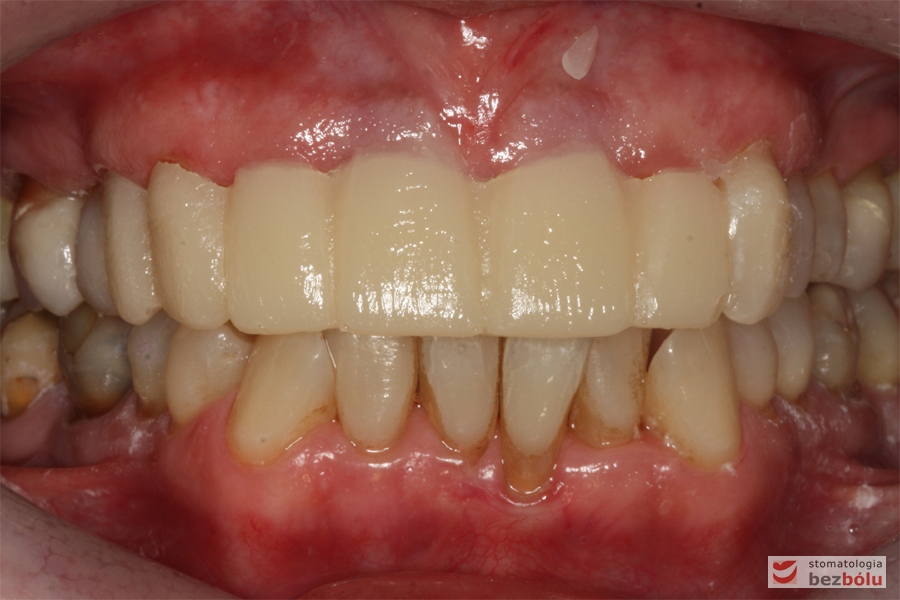

Oba łuki w zgryzie - przymiarka ostatecznej odbudowy protetycznej w jamie ustnej

Oba łuki w zgryzie – przymiarka ostatecznej odbudowy protetycznej w jamie ustnej